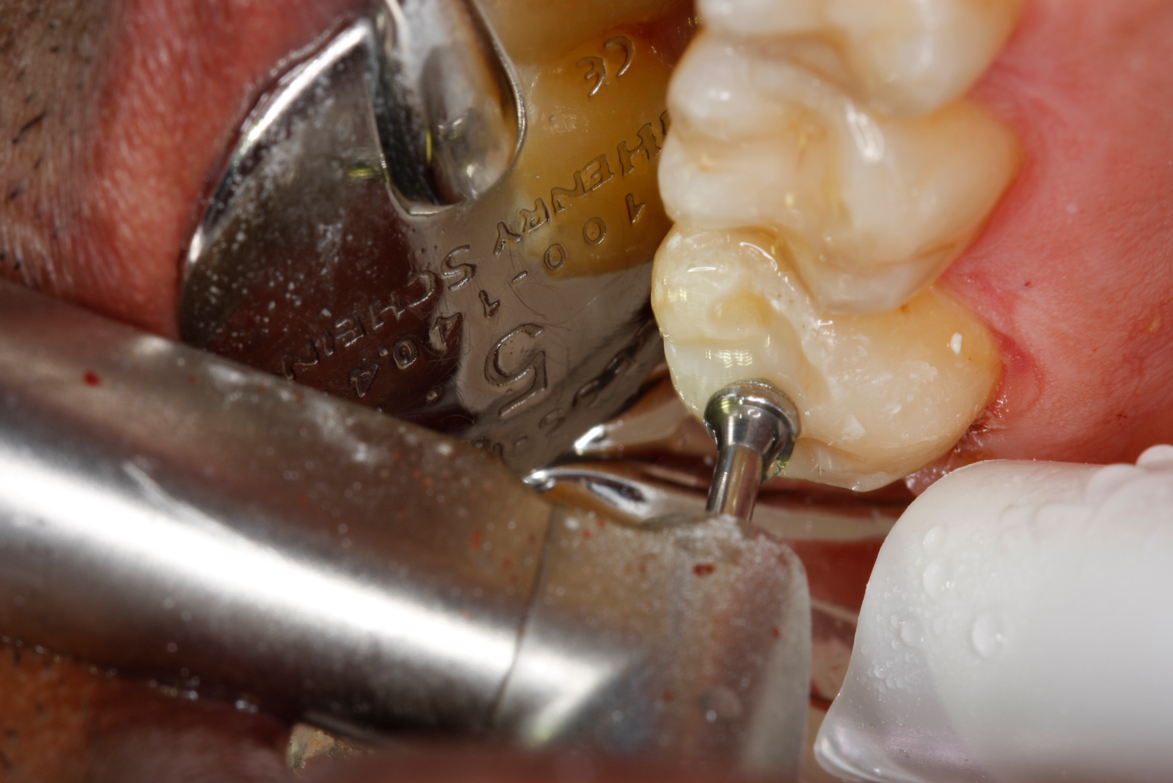

A deep distal occlusal preparation was performed and a matrix band (Paraband, Practicon) was placed again, such that no wedge needed to be placed (Figure 32). The Groman Etchmaster was utilized to remove biofilm as previously shown in Figure 12. A total etch technique with 37% phosphoric acid was employed (Figure 33), and after thorough rinse and damp dry, a universal adhesive (Scotchbond Universal, 3M) with MDP was applied and light-cured 40 seconds at 1,200 mw/cm2 due to the depth of the box form (Fig- ure 34). Figure 35 shows the dual-cure bulk-fill flowable composite (Bulk EZ Plus, Zest Dental Solutions) being injected into the deep box with a 20-gauge bendable needle. It is important to keep extrusion pressure on the plunger while withdrawing the needle to prevent bubbles or voids in the composite interface with the tooth structure. Overfilling by approximately 10% and smoothing the surface only with brushes promotes good marginal seal (Fig- ure 36). It is critical to not disturb the occlusal surface of any dual-cure bulk-fill flowable with an attempt to "soft sculpt," as that may create marginal voids.

After this dual-cure flowable's obligatory 90-second self-cure, hard sculpting with burs can begin. The Occlusinator PRO bur set (StraussUSA) was used to rapidly sculpt in planes after anatomical pits are placed at the depth of the limit stops on the burs; the clinician will appreciate the safe edges of the acorns and the safe zones on the X-mas tree burs. Figure 37 shows the medium acorn with a 50-micron diamond placing a pit where the distal marginal pit should be. It is apparent in Figure 38 that the limit stop on the acorn prevents cutting starting pits too deeply.

The safe-zoned X-mas tree with 15-micron diamond now completed the angles of the triangular and marginal ridge (Figure 39). Brownies and Greenies have convex sides requiring reshaping to a flat side so as not to create a concave surface when they are being used to final sculpt and finish (Figure 40). The straight-sided Brownie is used at 50,000 to 100,000 rpm with a copious water spray to final-shape what the diamond-coated acorn and X-mas tree bur have created (Figure 41). Brownies cut and polish composite but will only polish enamel, and are thus a true asset at a reasonable cost. Figure 42 shows the X-mas tree-shaped Greenie used at 100,000 rpm and with a copious water spray. TopDotz polisher on the latch bristle brush run at 20,000 rpm and without water will create a very high luster (Figure 43). Last, the cotton buff run dry at 20,000 rpm will afford a very high gloss (Fig- ure 44). The finished restoration is anatomic and high gloss (Figure 45 and Figure 46), and is ready for endodontic access with distal caries removed for an impervious seal. The post-treatment radiograph shows the root lesion restored and ready for endodontic treatment in this patient (Figure 47). Subsequent to endodontic therapy, margin elevation was planned to be accomplished using the dual-cure bulk-fill flowable and its requisite seal for the basement layer. Either a quartz fiber post or a Nayyar technique, again using the dual-cure flowable as the core, will provide truly minimal invasion.

Fig 37. The acorn bur is used to place the “pilot pit” in the distal marginal ridge area.

Figure 37

Fig 38. Pilot pit. The limit stop on the bur prevents over-carving.

Figure 38

Fig 39. X-mas tree diamond refines the triangular ridges formed by the acorn diamond.

Figure 39

Fig 40. Brownie is shaped like a X-mas tree to prevent concaving the surface.

Figure 40

Fig 41. Brownie is used at 50,000 rpm with copious water spray on the occlusal surface, following planes defined by the acorn and X-mas tree diamonds.

Figure 41

Fig 42. Greenie is used on the occlusal surface, following planes created by the acorn, X-mas tree, and Brownie.